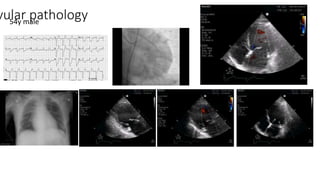

vular pathology54y male

vular pathology58y male